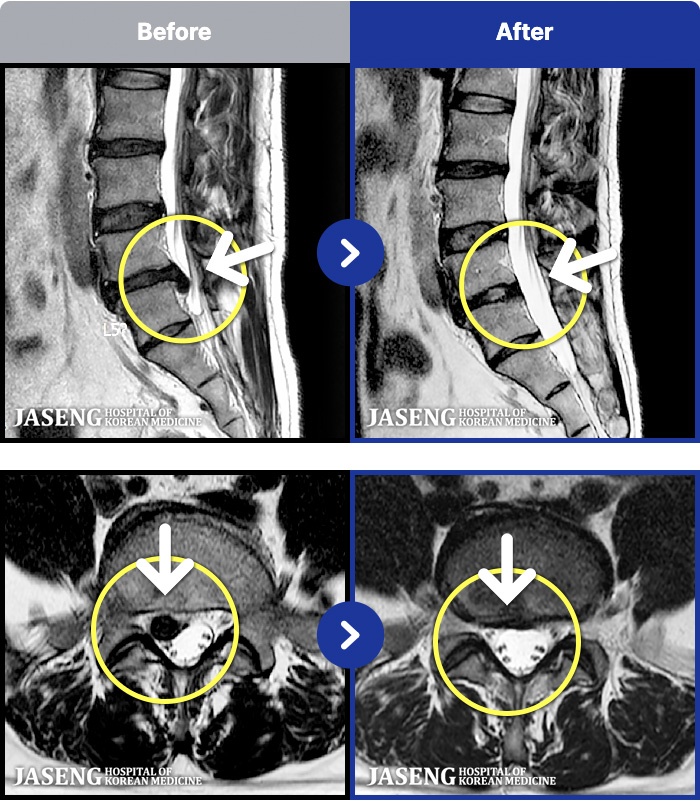

- MRI ġ

MRI ġ

181 MRI ũ ʸ Ȯϼ.

㸮 ϻ .